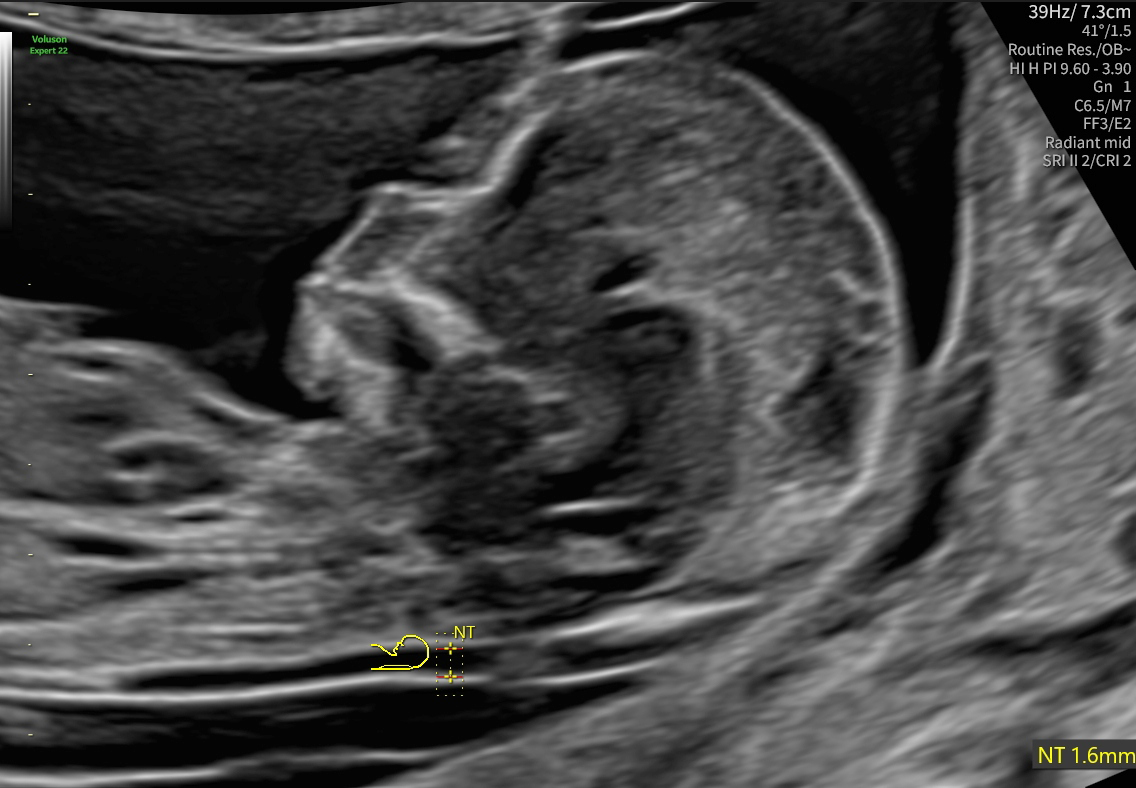

Die Besonderheit im ersten Trimester ist die Messung der Nackentransparenz (nuchal translucency, NT oder „Nackenfalte“ genannt), eine schmale Flüssigkeitsansammlung im Bereich des kindlichen Nackens, die in frühen Schwangerschaftswochen stets nachzuweisen und somit bis zu einem bestimmten Maß als normal anzusehen ist.

Mit Verbreiterung der Nackentransparenz steigt jedoch das Risiko für mögliche Erkrankungen des Feten, dies können sowohl organische als auch genetische Störungen sein.